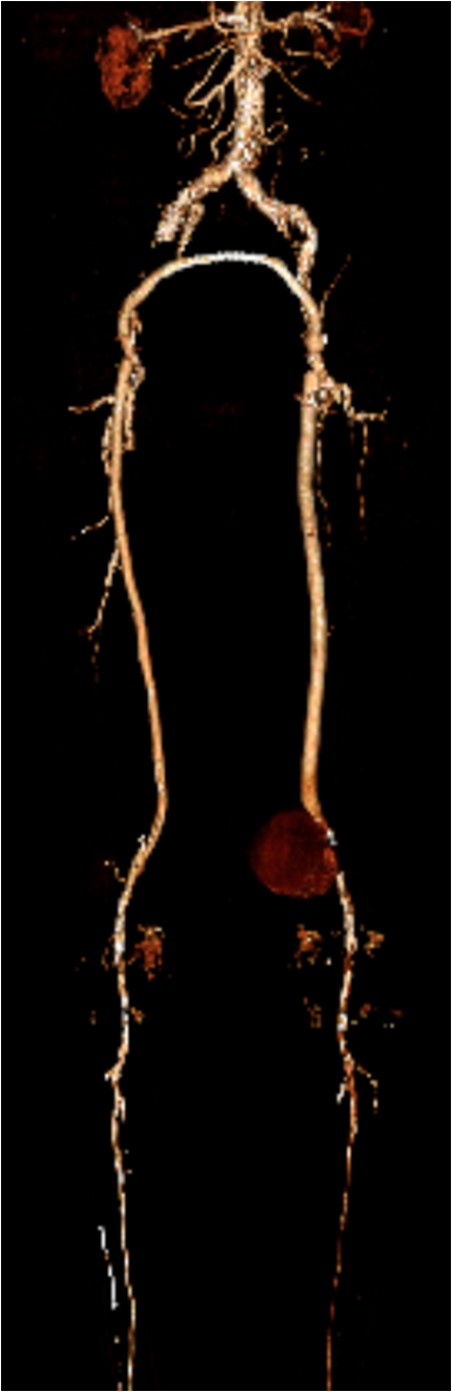

Coronal view of popliteal PS of distal anastomosis site of femoral–popliteal bypass.